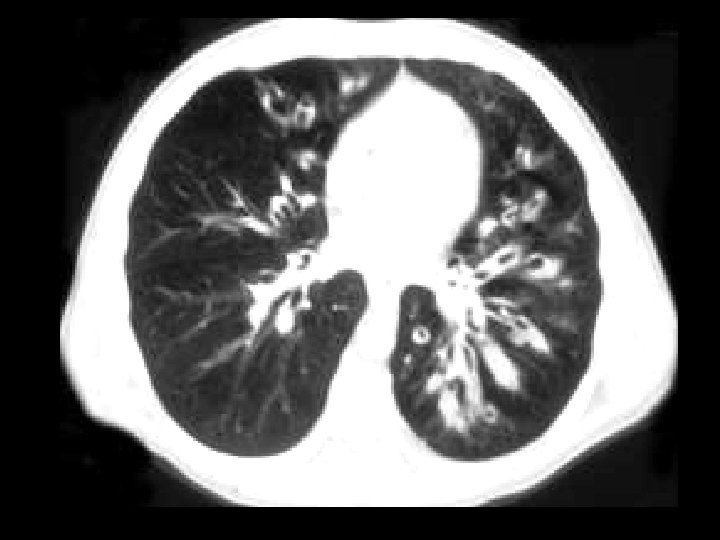

Pulmonary alveolar proteinosis • Findings: – Diffuse ground glass opacities of the secondary pulmonary lobules = “crazy paving” – Scatter thickening of the interlobular septa – Increased risk of Nocardia infection • Rx: BAL • ddx: – NONE! – This is an Aunt Minnie!